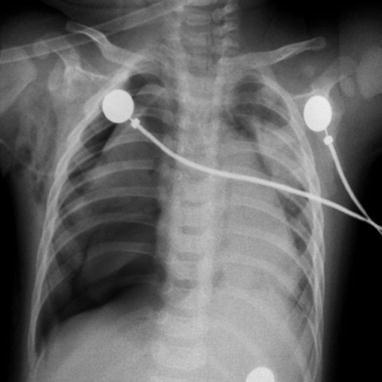

Measles Pneumonia in Children

Typical measles pneumonia in children is mainly characterized by interstitial inflammation, with grid-like lung markings. The lesions are mainly distributed in both middle and lower lungs with accompanying small spots and flakes of blurry shadows (Fig. 23.3). The common changes also include widened right upper mediastinum, increased transparency of lung fields, and emphysematous changes. The incidence rate of enlarged and thickened hilar shadow is higher in children than in adults.

Fig. 23.3.

Pediatric measles pneumonia. At day 4 after hospitalization, X-ray demonstrates thickened and blurry pulmonary markings in both lungs, small grid-like shadow at the middle and medial parts of left upper lung, and flakes of blurry shadows at the right lower lung hilum

Case Study 2

A girl aged 5 years complained of fever for 6 days as well as rashes, coughing with sputum for 4 days. Red maculopapules were observed at the face, chest, abdomen, back, and limbs.

Measles Pneumonia in Adults

Wang XQ et al. categorized measles pneumonia in adults into three types:

Reticular Type (Type I)

Type I is characterized by increased, thickened, and blurry pulmonary markings in reticular appearance, which are especially obvious at the middle and medial parts of the lung fields. Obstructive pulmonary emphysema can be found at both lungs.

Reticular and Small Nodular Type (Type II)

Based on type I, type II is characterized by extensive reticular shadow at both lungs, and small spots of blurry shadows along with bilateral pulmonary markings. The nodules have a diameter of 5–8 mm with poorly defined boundaries. The lesions are commonly distributed at the medial parts of the middle and lower lung fields. Obstructive pulmonary atelectasis can be found at both lungs.

Reticular, Small Nodular, and Infiltrative Type (Type III)

Based on type II, type III is characterized by small patches and flakes of blurry shadows along with bilateral pulmonary markings, which are especially obvious at the middle and medial parts of both lower lungs. The lesions are infiltrative with a size of 1–3 cm (Figs. 23.4, 23.5, 23.6, 23.7, and 23.8).

Fig. 23.4.

Adult measles pneumonia. X-ray demonstrates enhanced pulmonary markings at the right lower lung

Fig. 23.5.

Adult measles pneumonia. X-ray demonstrates diffuse ground-glass opacity at both lungs

Fig. 23.6.

Adult measles pneumonia. (a) X-ray demonstrates scattering flakes of ground-glass opacity at both lungs. (b) Reexamination after treatment for 3 days, CT scanning demonstrates multiple ground-glass opacity at both lungs, with paving stone-like lesions

Fig. 23.7.

Adult measles pneumonia. X-ray demonstrates large flakes of ground-glass opacity at the right lower lung

Fig. 23.8.

Adult measles pneumonia. X-ray demonstrates obviously increased and thickened bronchial shadows in both lungs